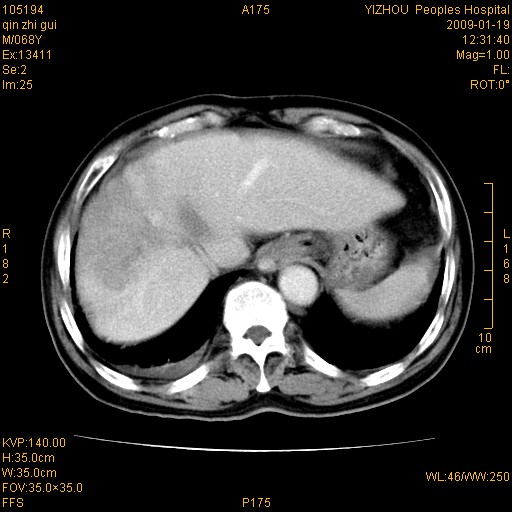

以下是引用随光逐影在2009-1-21 16:11:00的发言:[br]1)考虑肝右叶肝癌并肝静脉及门静脉瘤栓形成。2)肝硬化,少量腹水。3)胆囊炎。4)右侧少量胸腔积液。

病灶外缘凹凸不平,平扫低密度,增强动脉期有强化,门脉早显,静脉期及延期呈延迟强化,结合病史考虑右肝前叶巨块型肝癌可能性大,强化表现不除外胆管细胞癌